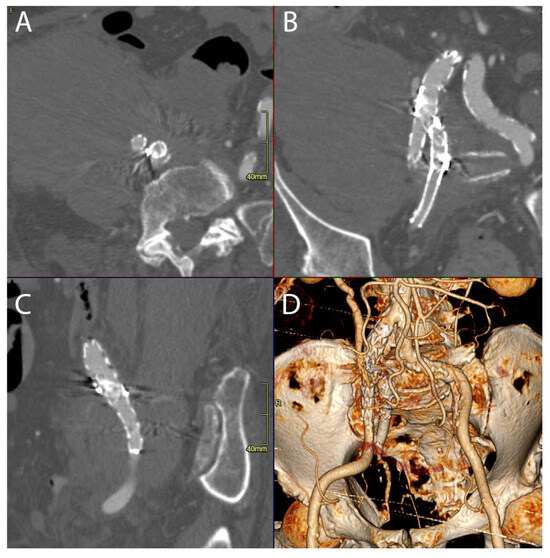

On the 30th postoperative day, the patient experienced a leakage from their rupture site that was a type Ia Endoleak (Figure 2), requiring an additional endovascular procedure to embolize the IIA and reline the common iliac and external iliac artery with an endograft.

Figure 2. Multiplanar reformation (MPR view in axial (A), coronal (B), sagittal (C)) and 3D reconstruction (D) of CT angiography demonstrating leakage from the right internal iliac artery rupture site due to a type Ia endoleak (highlighted with arrows).